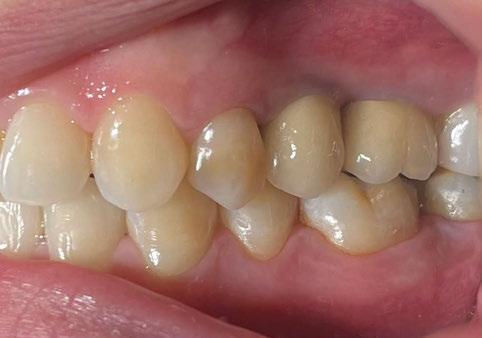

directamente a cabeza de implante para realizar una prótesis dentoalveolar de cerámica de 3 piezas, que equilibraran la oclusión y dieran soporte al labio y la mejilla (Figuras 14-17)

Durante el primer mes tras la intervención la paciente presentó epífora del ojo izquierdo que se resolvió de forma espontánea. Al año acude a consulta refiriendo dolor localizado y celulitis subcutánea originada por tejido de granulación en el brazo de la conexión más anterior.

Tras realizar curetaje quirúrgico periimplantario y tras una semana

de tratamiento antibiótico con amoxicilina y ácido clavulánico, cede la infección. Al segundo año de seguimiento, el tratamiento permanece estable y no ha presentado más complicaciones biológicas, estructurales o protésicas.

Figura 14. Imagen intraoral frontal postoperatoria al año de la reconstrucción.

Figura 15. Detalle de prótesis dentoalveolar cerámica en visión lateral.